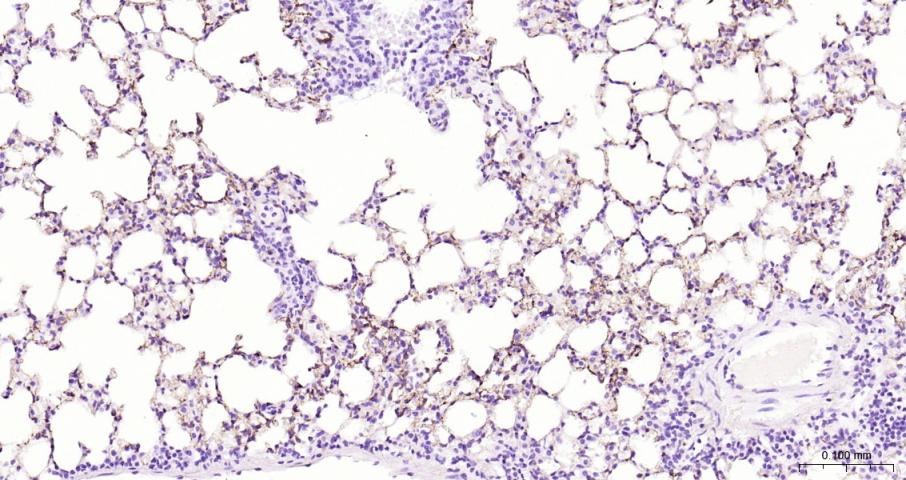

Paraformaldehyde-fixed, paraffin embedded Mouse lung; Antigen retrieval by boiling in sodium citrate buffer (pH6.0) for 15 min; Antibody incubation with ACE Monoclonal Antibody, Unconjugated(bsm-61652R) at 1:200 overnight at 4°C, followed by conjugation to the bs-0295G-HRP and DAB (C-0010) staining.